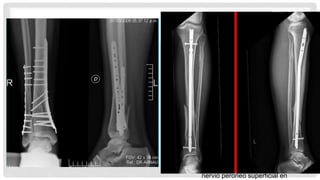

•Enclavado intramedular

•Indicaciones

•Suficiente hueso proximal para aceptar

dos tornillos de bloqueo (5-6 cm)

•Resultados

•Altas tasas de mala unión con una

técnica inadecuada

•Placa de fijación

percutánea

•Inadecuada fijación proximal para

IM clavado

El más adecuado para las fracturas

transversales u oblicuas

•mínimo compromiso de los tejidos

blandos

•Técnica

•Puede utilizarse medial o lateral

•Mejor cobertura de tejidos blandos

lateralmente hace planchas

laterales más seguro

•Enchapado lateral con

conminución medial puede

conducir a un colapso en varo

•Placas largas pueden colocar

nervio peroneo superficial en